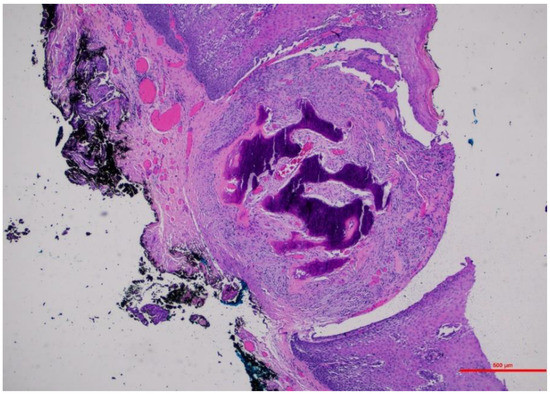

3.1.1. Case 1